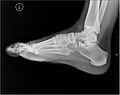

Žmogaus pėda yra sudėtingas mechanizmas, sudarytas iš kaulų, sąnarių, raumenų, sausgyslių, raiščių, nervų, kraujagyslių ir odos. Tipiškai pėdoje yra:

- 26 kaulai (7 tarsaliniai — tarp jų pėdos kulnas ir bėgis, 5 metatarsaliniai ir 14 falangų pirštams),

- apie 33 sąnarius ir daugiau nei 100 raumenų, sausgyslių ir raiščių, kurie kartu kontroliuoja judėjimą ir stabilumą,

- plantarinė fascija (plantaris fascija) — stiprus raištis, kuris palaiko pėdos skliautus ir amortizuoja smūgius,

- Achilo sausgyslė, jungianti blauzdos raumenis su kulnakauliu (kulnu),

- stipri odos ir riebalinio audinio pagalvėlė pėdos apačioje, apsauganti kaulus ir minkštuosius audinius nuo spaudimo.

Pėdoje yra trys pagrindiniai skliautai:

- medialinis skliautas (aukštas vidinis skliautas),

- laterinis skliautas (šoninis, žemesnis),

- transversinis skliautas (pereinantis per pėdos plotį).